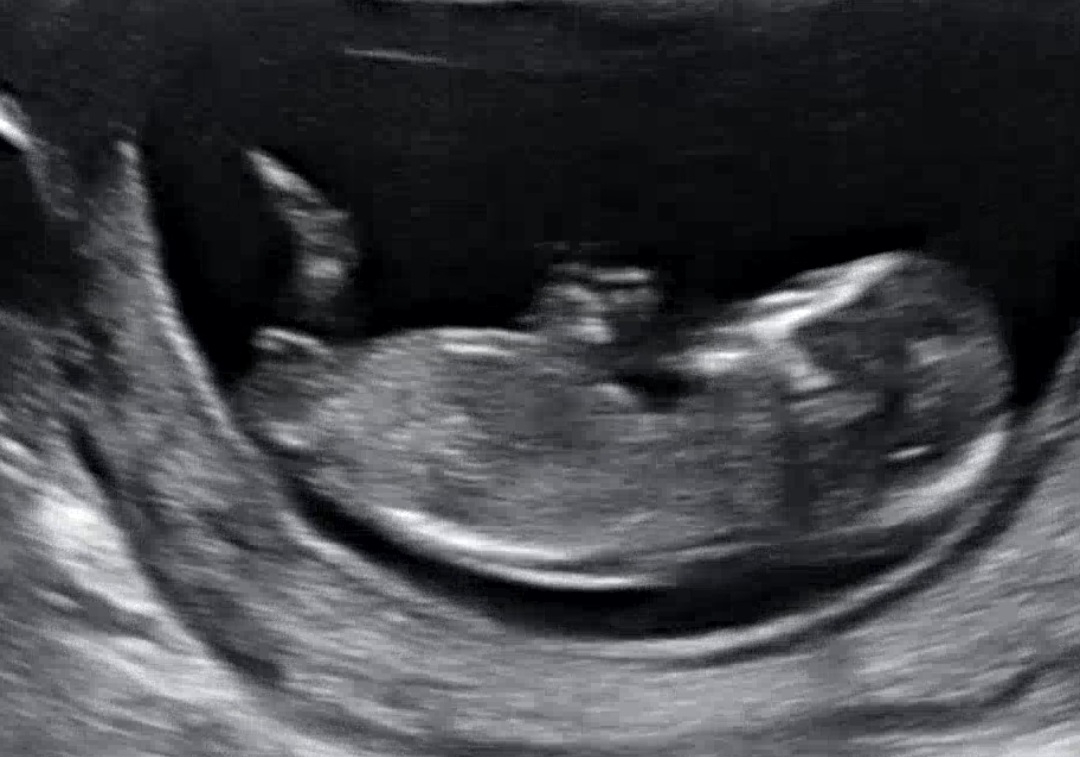

12주3일 각도법으로 봐선 어떤가요?

각도법으로 봐선 어떤가요?^^